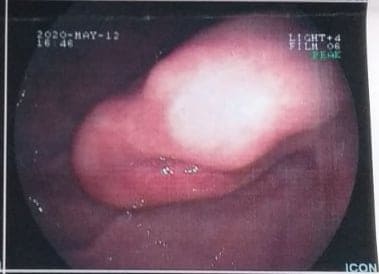

Στην πρώτη φωτογραφία:

Πρώτη διάγνωση με ενδοσκόπηση ανώτερου συστήματος: Έμμισχος πολύποδας στομάχου 5 εκ

Δεύτερη γνώμη της Ενδοσκοπικής μας Μονάδας (φώτο 2,): Υποβλεννογόνιο Μόρφωμα στομάχου 5 εκ. (όγκος κάτω από την επιφάνεια του βλεννογόνου), ο οποίος αφαιρέθηκε επιτυχώς και εξ’ ολοκλήρου από τον διευθυντή της Ενδοσκοπικής Μονάδας Πειραιά, Dr. Σταύρο Καρακατσάνη.